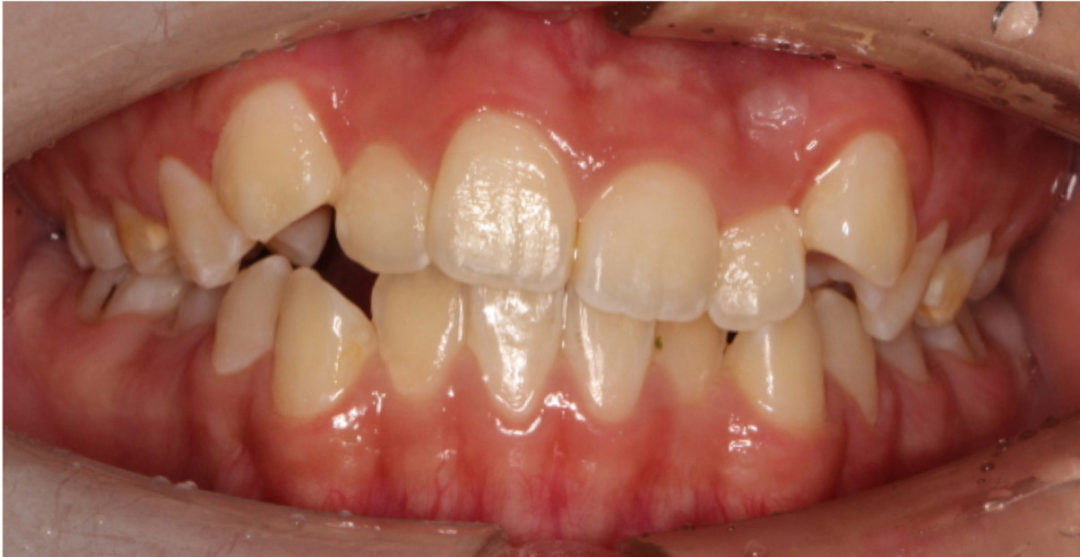

如果孩子闭锁性深覆合的问题,尤其是上前牙覆盖下前牙,甚至内扣盖住下前牙,如果孩子是高角或者是高角偏均角的话,这个就容易出现未来下颌骨发育的受限。

但如果发现是典型的低角,那么孩子颏部形态长得会比较好,只是因为下前牙唇倾会导致下巴被迫后退,当早期矫正改善下前牙位置后,孩子的下巴自然而然就会出来了。

其实这也是错颌畸形先天基因的表达和后天相关影响,这两个因素作斗争时谁会更强的结果吧。因此出现闭锁性深覆合,在5岁左右或者替牙期换完上下门牙时进行矫正,可以引导牙齿和颌骨的正常生长,还有机会改变骨骼生长型。在生长发育过程中,由于遗传因素、环境因素、口呼吸习惯等导致颌骨发育异常,会出现上颌前凸、下颌后缩、腭盖高拱、腺样体面容等问题。